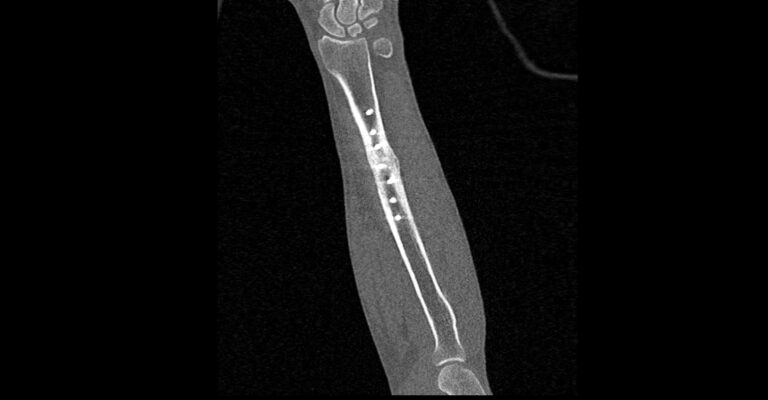

В диагностических центрах «Доступная медицина» сканирование области предплечья проводится на современных мультиспиральных компьютерных томографах экспертного класса TOSHIBA AQUILION. Аппараты при помощи рентгеновских лучей послойно сканируют исследуемую область, делая одномоментно множество тончайших срезов толщиной от 0,5 мм. В результате получаются детализированные изображения высокого уровня четкости и контрастности, при этом томографы обеспечивают минимум лучевой нагрузки на организм пациента.

Полученные при сканировании данные в дальнейшем проходят цифровую обработку, и на их основе создаются трехмерные изображения области предплечья.

Мультиспиральная КТ позволяет диагностировать деформации костей на фоне аномалий развития, различные вывихи, переломы костей предплечья, ушибы мягких тканей и надкостницы. КТ помогает обнаружить участки деструкции костной ткани, воспалительные изменения, опухолевые процессы. Результаты КТ дают информацию для хирурга и травматолога перед операцией о расположении осколков кости, а после операции позволяют оценить правильность репозиции костных отломков, проследить процессы регенерации кости, вовремя выявить различные осложнения (воспаление, смещение отломков, очаги деструкции костной ткани).